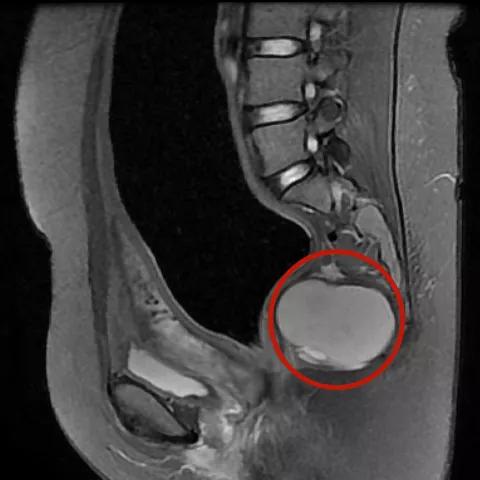

她的骶尾部还有个苹果大小的 囊性占位

△骶尾部囊性占位

同时 还要把她骶尾部的囊性占位“清除”!

由于骶尾部骶前血管一旦破裂很难止血

所以在切除骶尾部囊性肿瘤时

需要丰富的经验技术

术中专家团队 成功剥离肿瘤